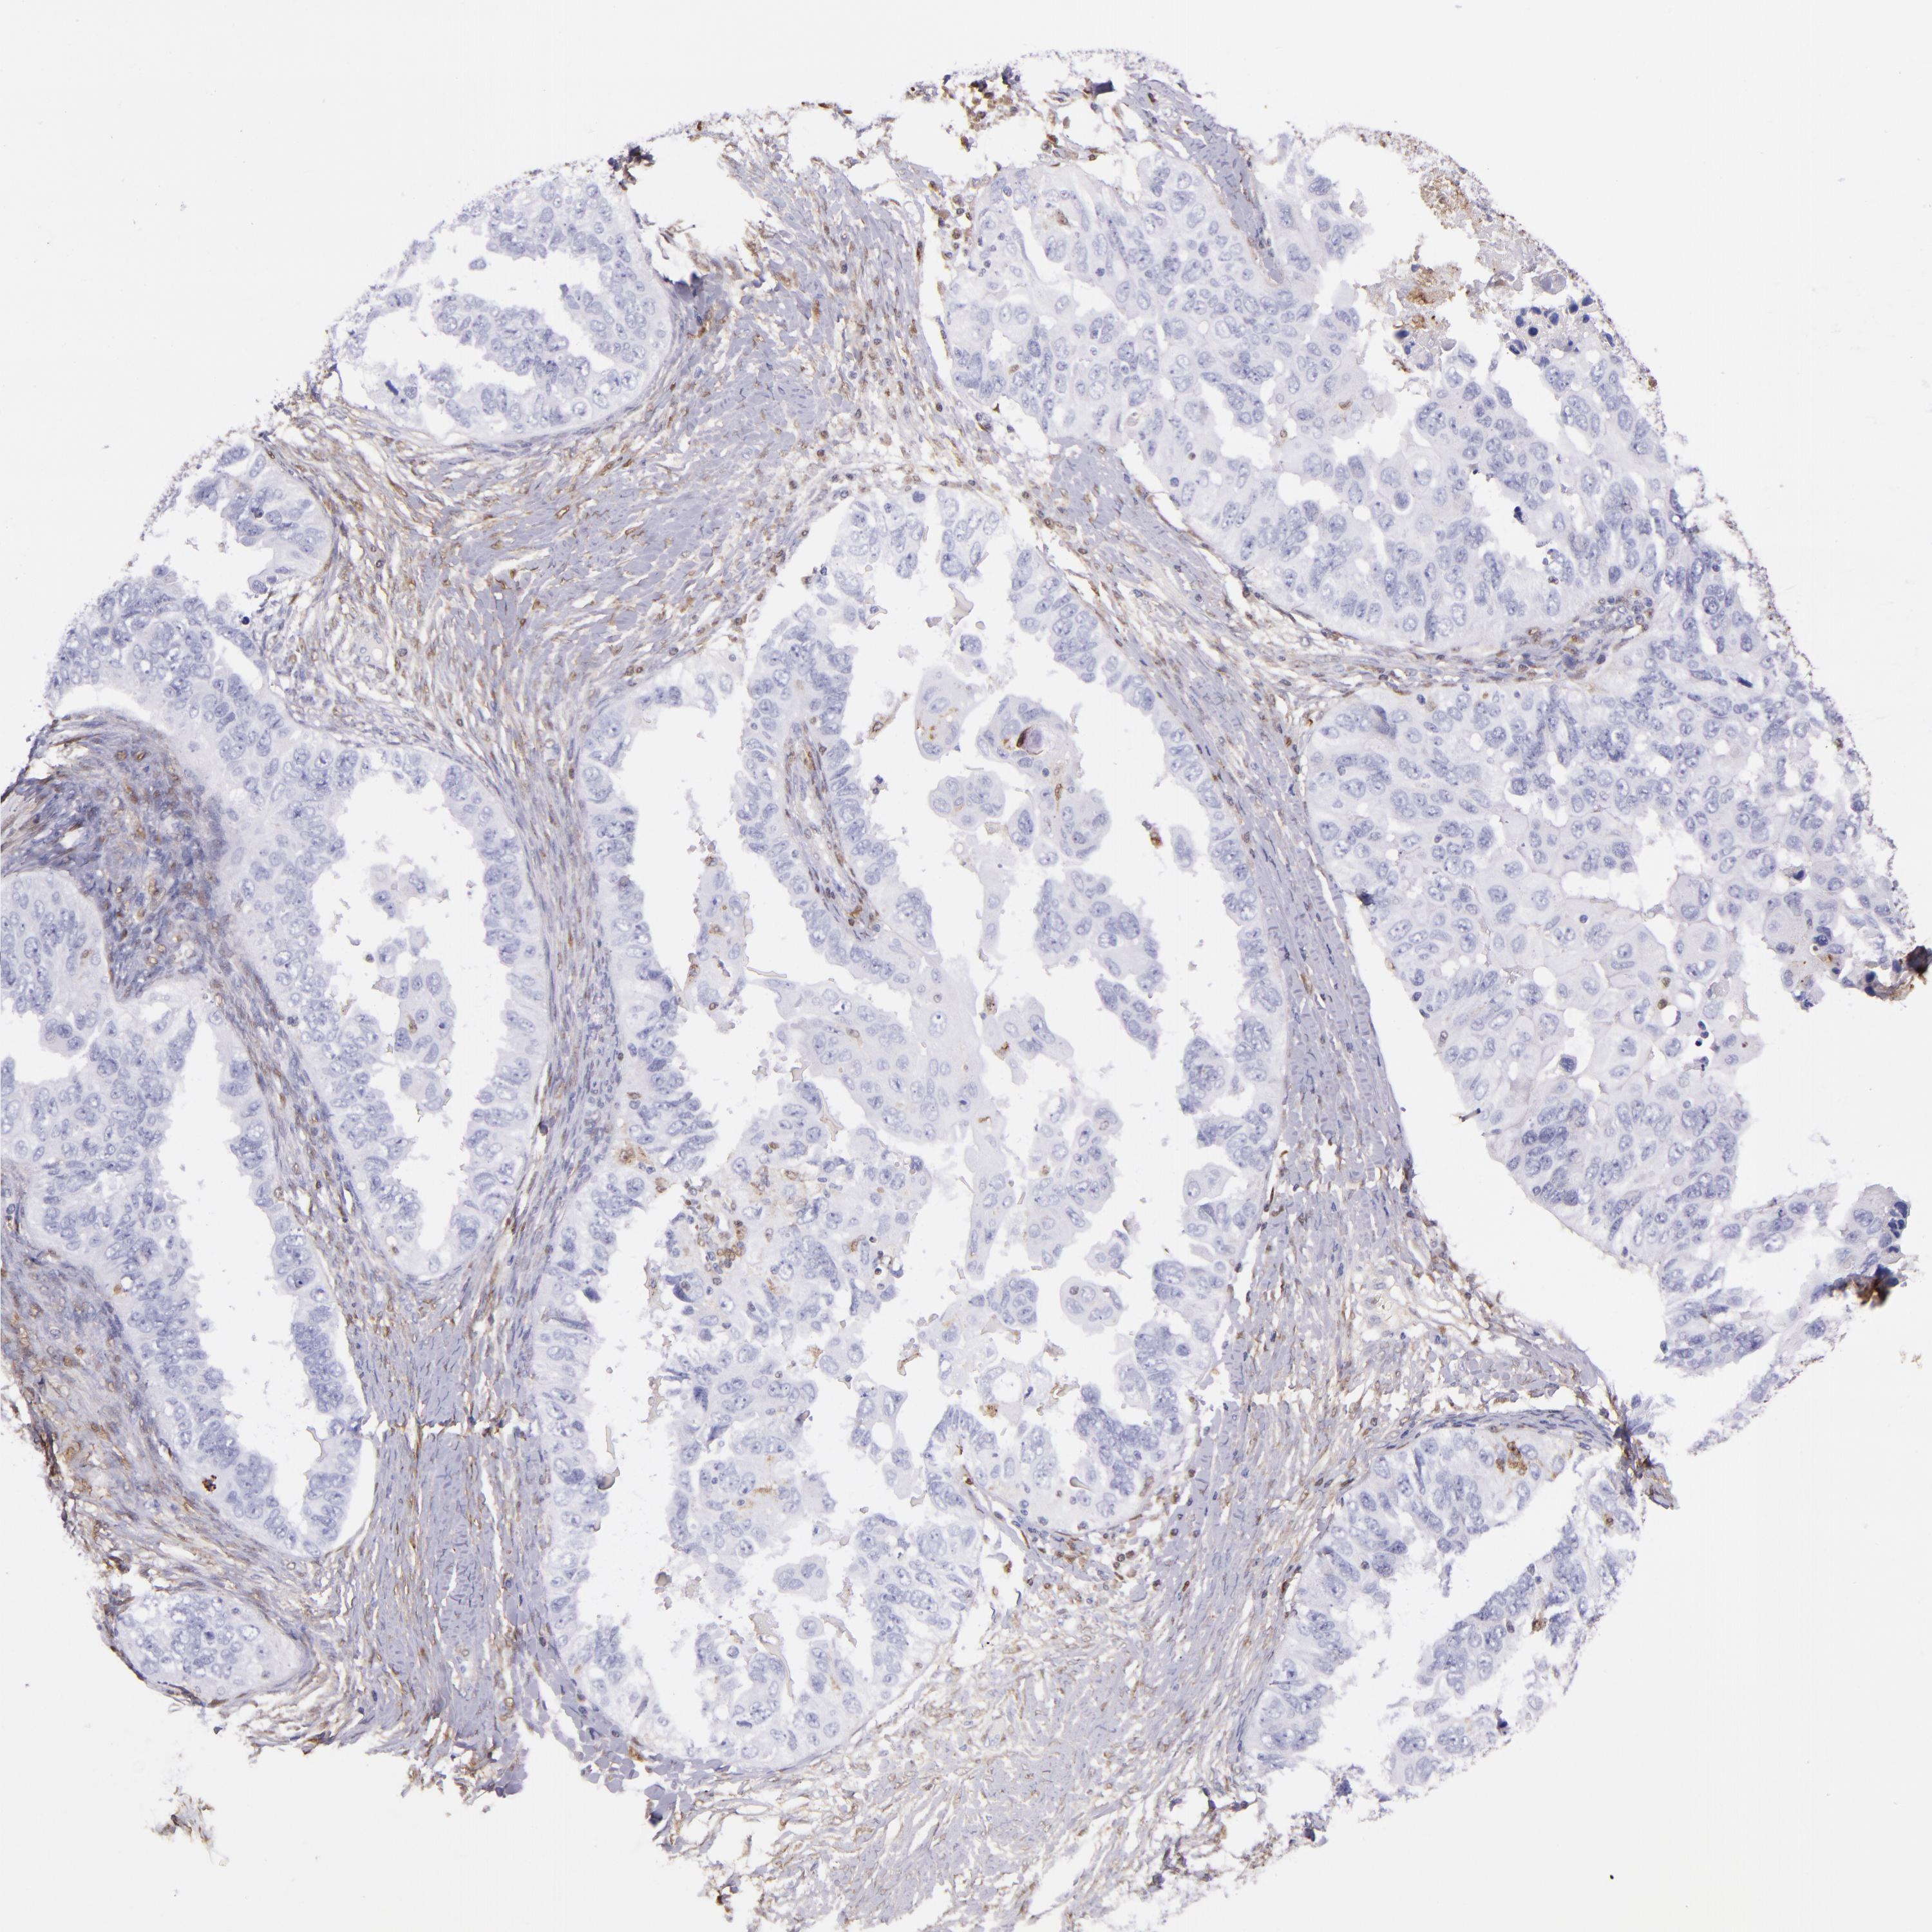

OVARIAN CANCER - Protein expressioni

A mouse-over function shows sample information and annotation data. Click on an image to view it in a full screen mode. Samples can be filtered based on level of antibody staining by selecting one or several of the following categories: high, medium, low and not detected. The assay and annotation is described here.

Note that samples used for immunohistochemistry by the Human Protein Atlas do not correspond to samples in the TCGA dataset.

Antibody stainingi

Antibody staining in the annotated cell types in the current human tissue is reported as not detected, low, medium, or high, based on conventional immunohistochemistry profiling in selected tissues. This score is based on the combination of the staining intensity and fraction of stained cells.

Each image is clickable and will lead to virtual microscopy that enables deeper exploration of all samples and also displays staining intensity scores, fraction scores and subcellular localization as well as patient and tissue information for each sample.

Cystadenocarcinoma, serous, NOS